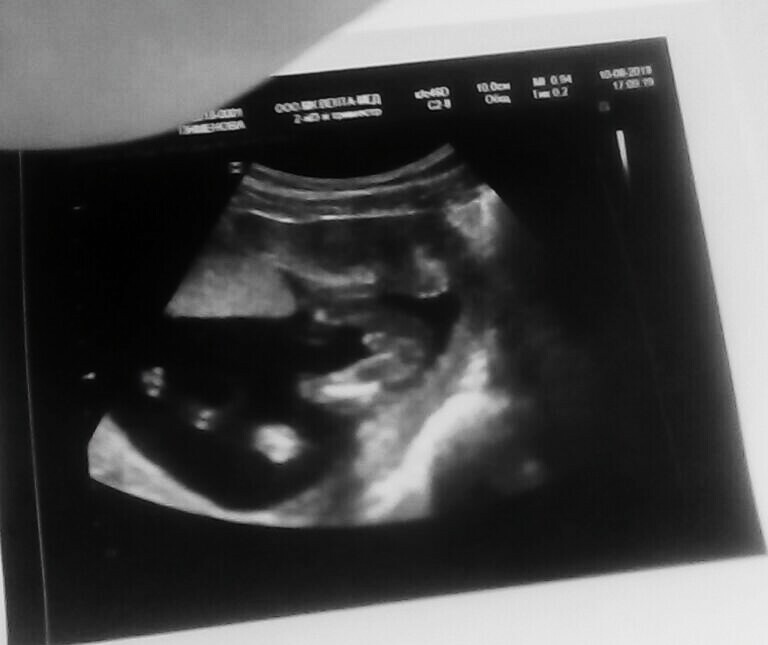

УЗИ, КТГ, доплерПрошли мы 2 скрининг,все хорошо с малышом.Так подрос,такой любимый и ,самое главное ,здоровый))) ииии.... сказали нам,что 100%девочка.Я показала предыдущее фото с двух узи из разных мест,где нам показали мальчика.Разница между узи 10 дней.Меня спросили:а фото точно твое?Говорю мое,видела все в экран.На что мне сказали,что пол узнаю после родов,но сегодня-девочка))))Так не интересно.....

Самое интересное,что на узи 22 июля рост 15,4см,а 6 августа 10,1 см.Уменьшился.Либо кто-то из узистов явно криворукий